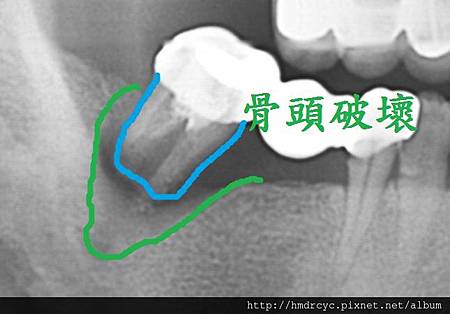

牙周病不管在假牙或自然牙齒

都必須X光來診斷嚴重程度

而牙周病最可怕的部分就是造成骨頭破壞

有時候外表看起來不錯的牙齒

其實裡面骨頭以經破壞嚴重甚至造成動搖

嚴重者骨頭以經完全破壞

牙齒失去支撐 就會浮起來

這時就只能考慮拔除

在牙橋有時感覺動搖度並不大

那是因為跟其他牙齒聯結在一起的關係

單顆牙齒骨頭破壞嚴重就會馬上出現動搖

骨頭破壞後原本骨頭位置被發炎的肉取代

甚至形成膿包